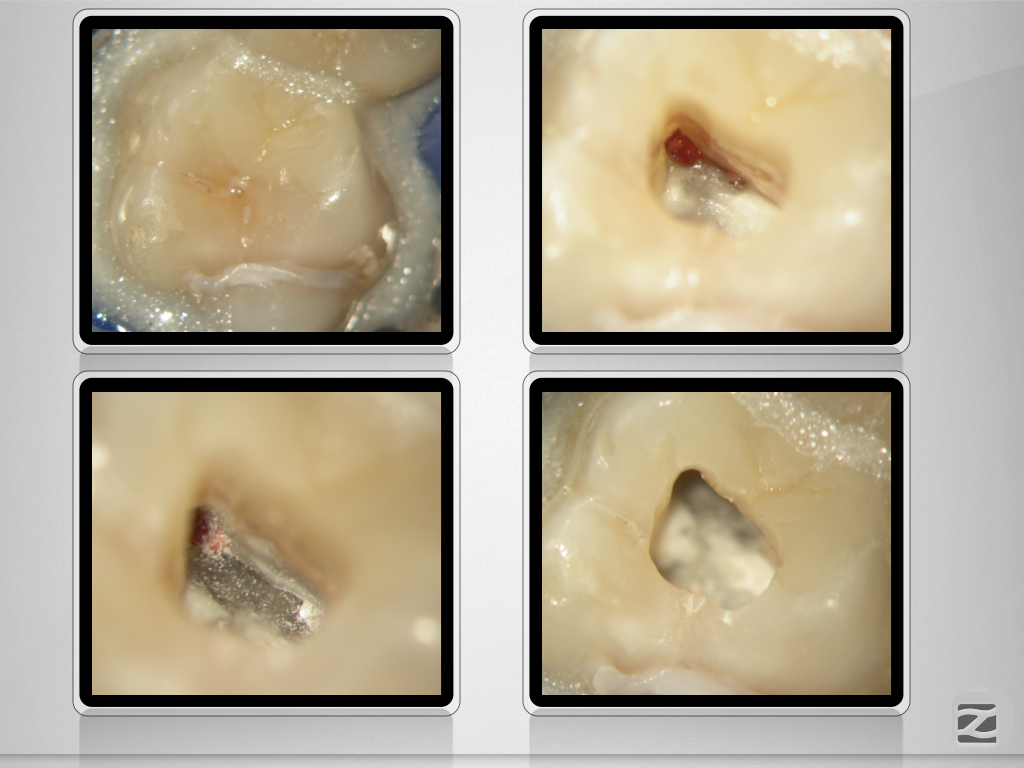

26D.007

Fluch und Segen!